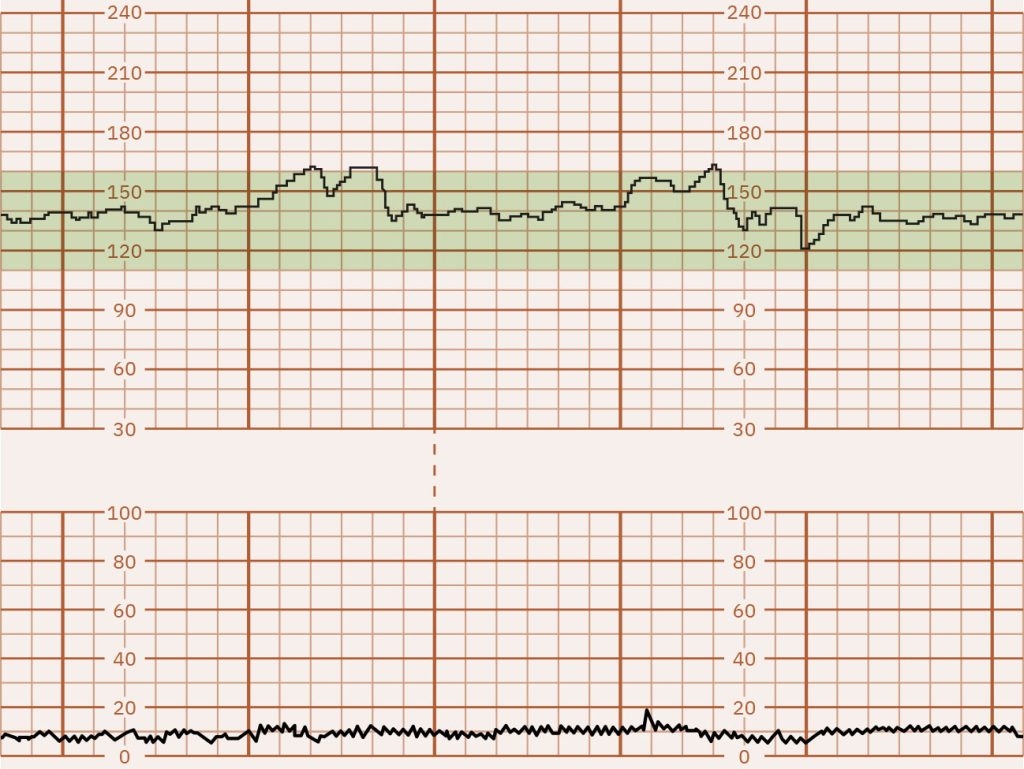

10 5 Fetal Heart Rate Monitoring Nursing Health Promotion